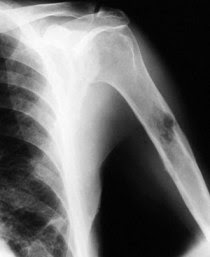

Next, your doctor will likely order some imaging studies (imaging). X-rays are often ordered first. In some cases, if cancer is identified very early it might not show up on plain x-rays. The appearance of a tumor on x-rays can help determine the type of cancer and whether it is benign or malignant. Benign tumors are more likely to have an edge (boundary) is smooth where malignant tumors are more likely to have a ragged edge. This is because benign tumors typically grow more slowly and the bone has time to try to surround the tumor with normal bone. Malignant tumors are more likely to grow more quickly, not giving the normal bone a chance to surround the tumor.